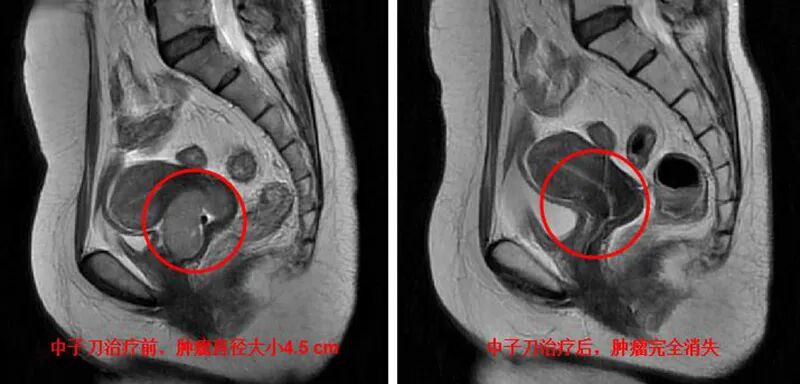

▲治疗中的张阿姨

因为病情不断加重,张阿姨出现了大出血。后来通过一个病友介绍,来到了北部战区总医院和平院区放射治疗科就诊,周凤佳主治医师仔细查看了她的资料,结合临床检查,建议进行盆腔外照射联合中子刀治疗,并向张阿姨及家属详细介绍了治疗方案及注意事项。张阿姨一家人接受了建议,积极配合,顺利完成了治疗,直径4.5厘米的肿瘤完全消失。治疗后张阿姨的生活基本恢复正常,并重新回到了工作岗位。目前每3个月复查一次,每次复查都能看到张阿姨的笑脸和她对中子刀治疗的感叹,“刚开始我还有些紧张,到后来发现没什么痛苦,我经常治着治着就睡着了,一觉醒来,治疗也结束啦!”

▲中子刀治疗后复查,肿瘤完全消失